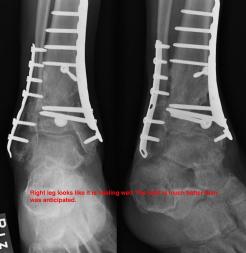

Post-infection X-Rays of the damaged right & left legs / ankles

After the last surgery Liam developed Staphylococcal (staph) infection as well as Osteomyelitis on the bone. Liam went to the ER of

Tempe St. Luke with a temperature of over 104 degrees and severe pain of the left leg. Liam was released from the ER with a diagnosis of

Gastroenteritis and instructions to follow up with a visit to Dr. Armendariz. Four days later and with a continued very high temp, Liam was

seen by Dr. Armendariz. Dr. Armendariz immediately performed 3 surgeries to clean out the infected areas of both the left and right leg and

to place wound vacs on the damaged areas of the legs.

An interesting point to note, as it applies to the second and third x-rays (from the left), is the placement of the last screw at the bottom

of the right legs fibula plate. Notice how Dr. Keller completely missed the plate. Not only is the screw useless, but it has started protruding

in such a way as to cause severe pain and require padding to keep from bursting through the skin. A later surgery is planed for the screws

removal.